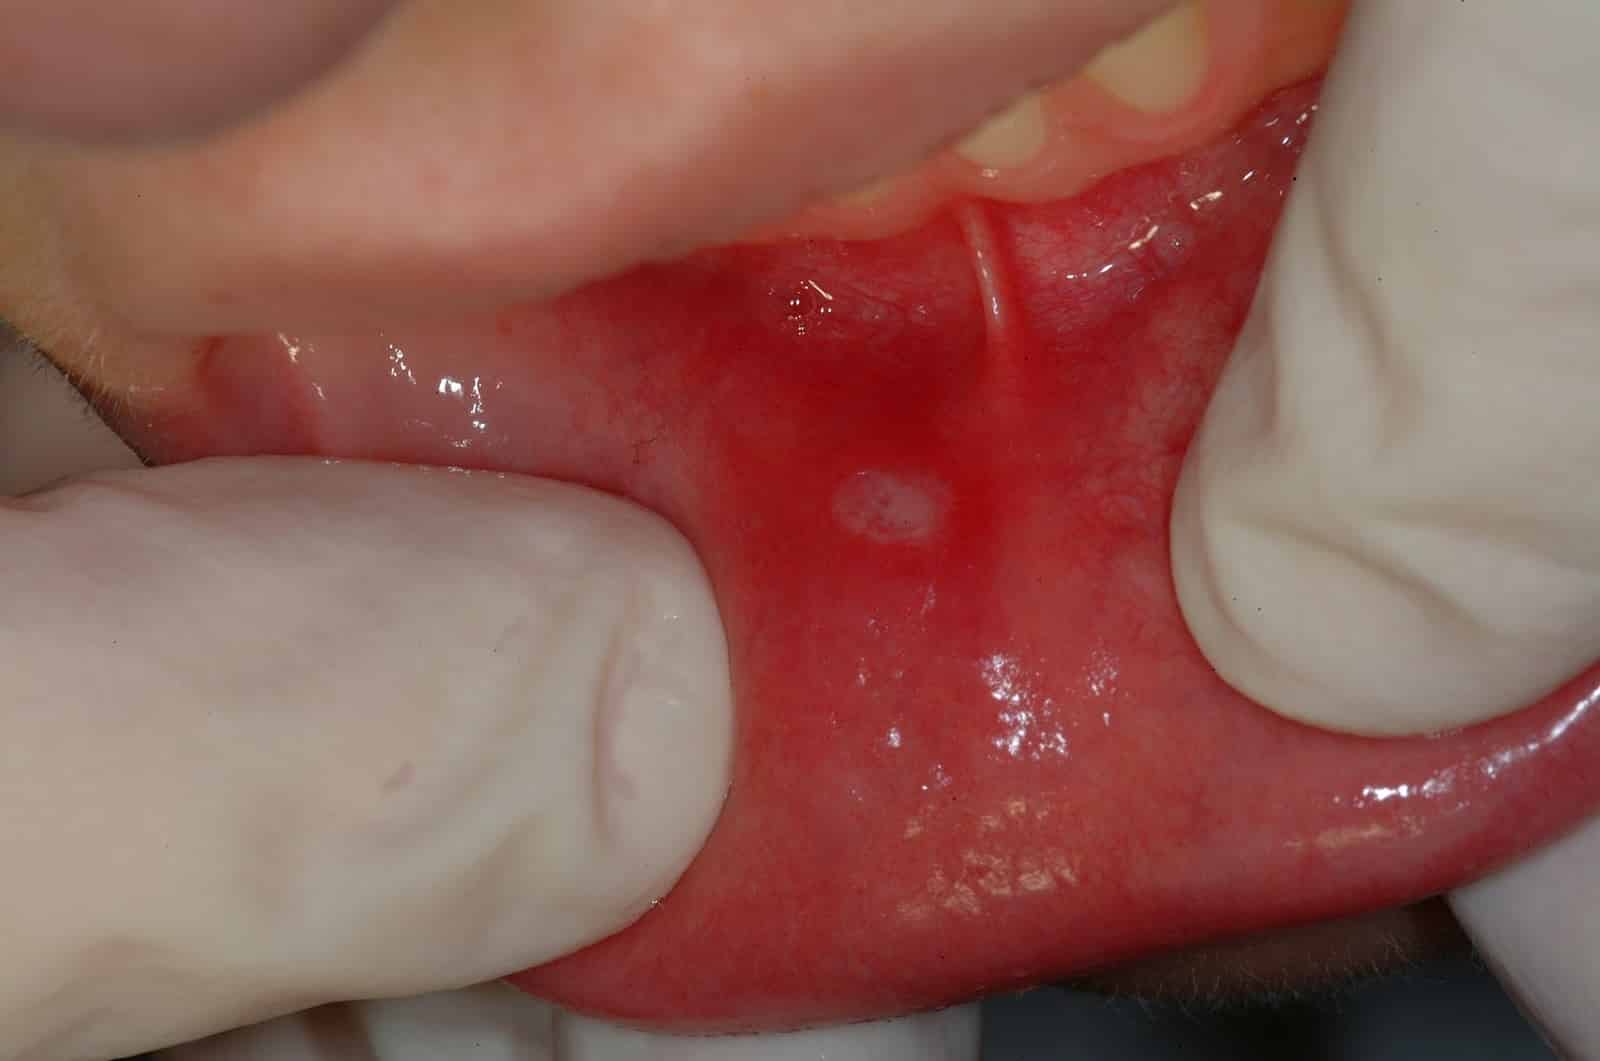

Бактериальное поражение

Бактериальный стоматит Бактериальная форма одна из наиболее часто встречающихся у детей. Признаки стоматита у ребенка:

- Отечность и покраснение слизистой оболочки щек, языка, внутренней поверхности губ и неба. На ней могут образовываться трещинки, язвочки.

- Появляется неприятный запах изо рта, может слегка повыситься температура, возникнуть слабость (см. также: почему у ребенка появился неприятный запах изо рта?).